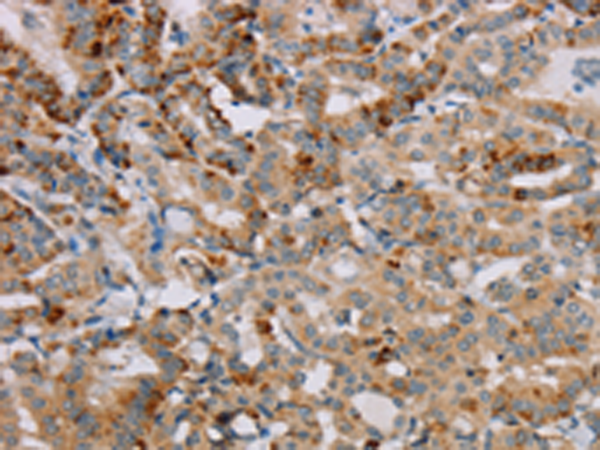

分类: 科研抗体货号: P08539别名: Bex; NADE; HGR74; NGFRAP1; DXS6984E应用: IHC反应种属: Human